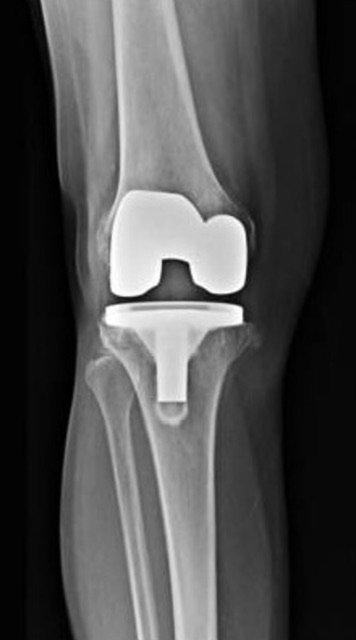

Once the patient is under anesthesia, the surgeon will make an incision in the knee area to access the knee joint. The length and location of the incision may vary depending on the patient's knee condition and the type of knee replacement being used. Typically, patients will have a traditional incision as seen in the picture below, but there are many other options surgeons perform based on the patients goals and request.

The surgeon will then attach the artificial components to the prepared bone surfaces using a special surgical adhesive or cement. The cement or adhesive will be a crucial part in the longevity of your total knee replacement. The metal knee implants or artificial components typically consist of a metal alloy or ceramic material. Then in between the metal knee parts is a plastic spacer or polyethylene spacer that reduces metal on metal noise and friction. The plastic spacer that acts as a cushion between the two metal components. You can imagine how noisy it would be without the plastic piece!